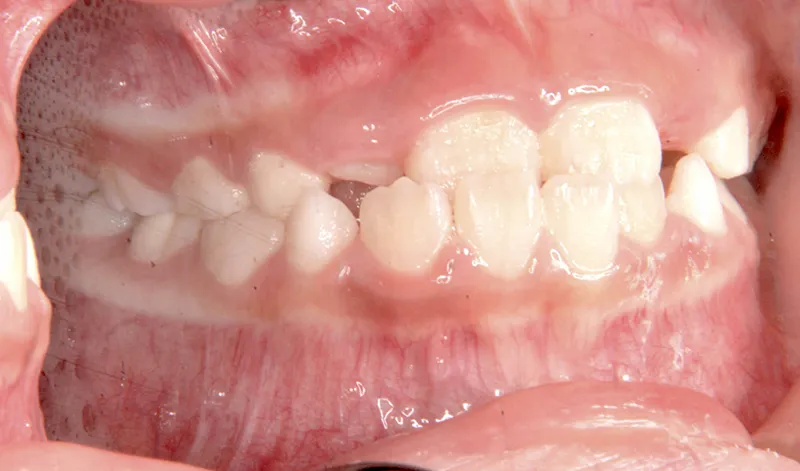

初診時年齢 小学校1年生 (女性) 主訴 受け口

診断名 叢生・反対咬合 装置名

状態 永久歯が生える隙間がない(叢生)

受け口(下顎前突/反対咬合)

下顎が大きい傾向があります。

上下の真ん中にズレがあるのと、上下とも永久歯の生えるスペースがせまいため、オリジナル矯正装置でスペースを作り、受け口も改善していきます。